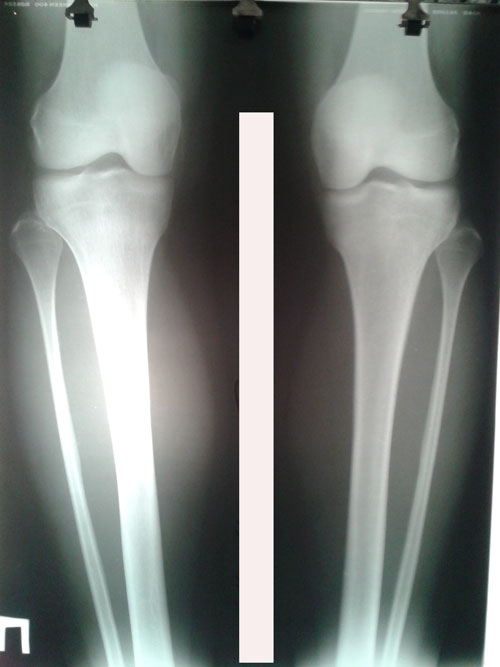

Дата операции 06.05.2016г.

Дата снятия аппаратов 13.08.2016г.

Срок лечения 97 дней.

Обратите внимание, как мастерски исправлена ротация!